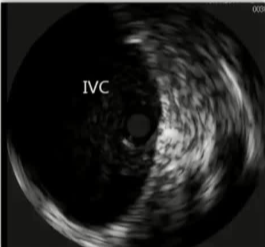

![]() if you look hard enough,如果你的眼睛睁的足够大,你就不难发现,通常下肢血栓清除后是潜在的静脉狭窄 术前的影像检查能为您提供一些线索:可能存在动脉受压的情况;或者淋巴结或其他肿块压迫了静脉。 血栓的上限通常标志着狭窄的部位。 术中血管内超声检查是最准确的。

2. 如果没有血管内超声技术,预扩张则有助于实现支架尺寸的精确测量。【Oropallo 2023】【CIRSE SOP 2014】 3. 必须确保支架输送系统能够顺利通过并完成置入操作。【Oropallo 2023】【CIRSE SOP 2014】